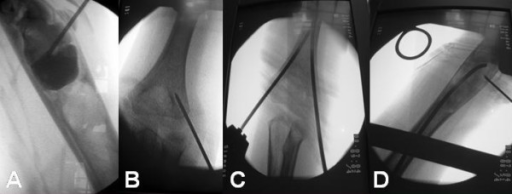

AP radiograph of the proximal humerus demonstrating a unicameral bone cyst (simple bone cyst) complicated by a pathological fracture. The lesion presents as a centrally located, lytic metaphyseal defect with thinning of the overlying cortex. This image originates from a study on elastic intramedullary nailing for such lesions.

Source: Simple Bone Cyst Pathological Fracture • PMC2117015 • CC-BY